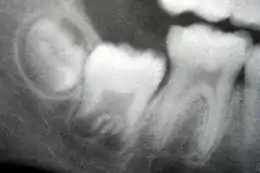

La dentition mixte commence lorsque la première molaire permanente apparaît dans la bouche, généralement à six ans, et dure jusqu'à ce que la dernière dent de lait soit perdue, le plus souvent à onze ou douze ans[29]. Les dents permanentes du maxillaire sortent dans un ordre différent des dents permanentes de la mandibule. Les dents du maxillaire sortent dans l'ordre suivant : (1) première molaire (2) incisive centrale, (3) incisive latérale, (4) première prémolaire, (5) deuxième prémolaire, (6) canine, (7) deuxième molaire et (8) troisième molaire. Les dents de la mandibule sortent dans l'ordre suivant : (1) première molaire (2) incisive centrale, (3) incisive latérale, (4) canine, (5) première prémolaire, (6) deuxième prémolaire, (7) deuxième molaire, et (8) troisième molaire. Comme il n'y a pas de prémolaires dans la dentition primaire, les molaires primaires sont remplacées par les prémolaires permanentes[30]. Si les dents primaires sont perdues avant que les dents permanentes ne soient prêtes à les remplacer, les dents postérieures peuvent se déplacer vers l'avant et réduire l'espace disponible pour la future dent[31]. Cela peut provoquer des chevauchements et/ou des malpositions des dents permanentes, ce qu'on appelle généralement « malocclusion ». Une orthodontie peut être alors nécessaire dans de telles circonstances pour réaligner les dents.

La dentition permanente commence lorsque la dernière dent de lait est tombée, habituellement à 11 à 12 ans, et dure jusqu'à la fin de la vie d'une personne ou jusqu'à ce que toutes les dents soient perdues (édentation). Durant cette phase, les troisièmes molaires (aussi appelées dents de sagesse) sont souvent extraites en raison d'infections locales, de douleurs à l'éruption ou d'impactions dentaires. Les principales raisons de la perte des dents sont la carie et la maladie parodontale[32].